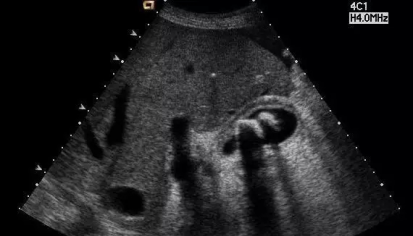

“大夫,听说不吃早餐容易得胆囊结石。是真的吗?”在临床为患者做B超检查时,经常会遇到患者这样问。其实,经常不吃早餐,真的就是引发胆结石的一个重要原因。